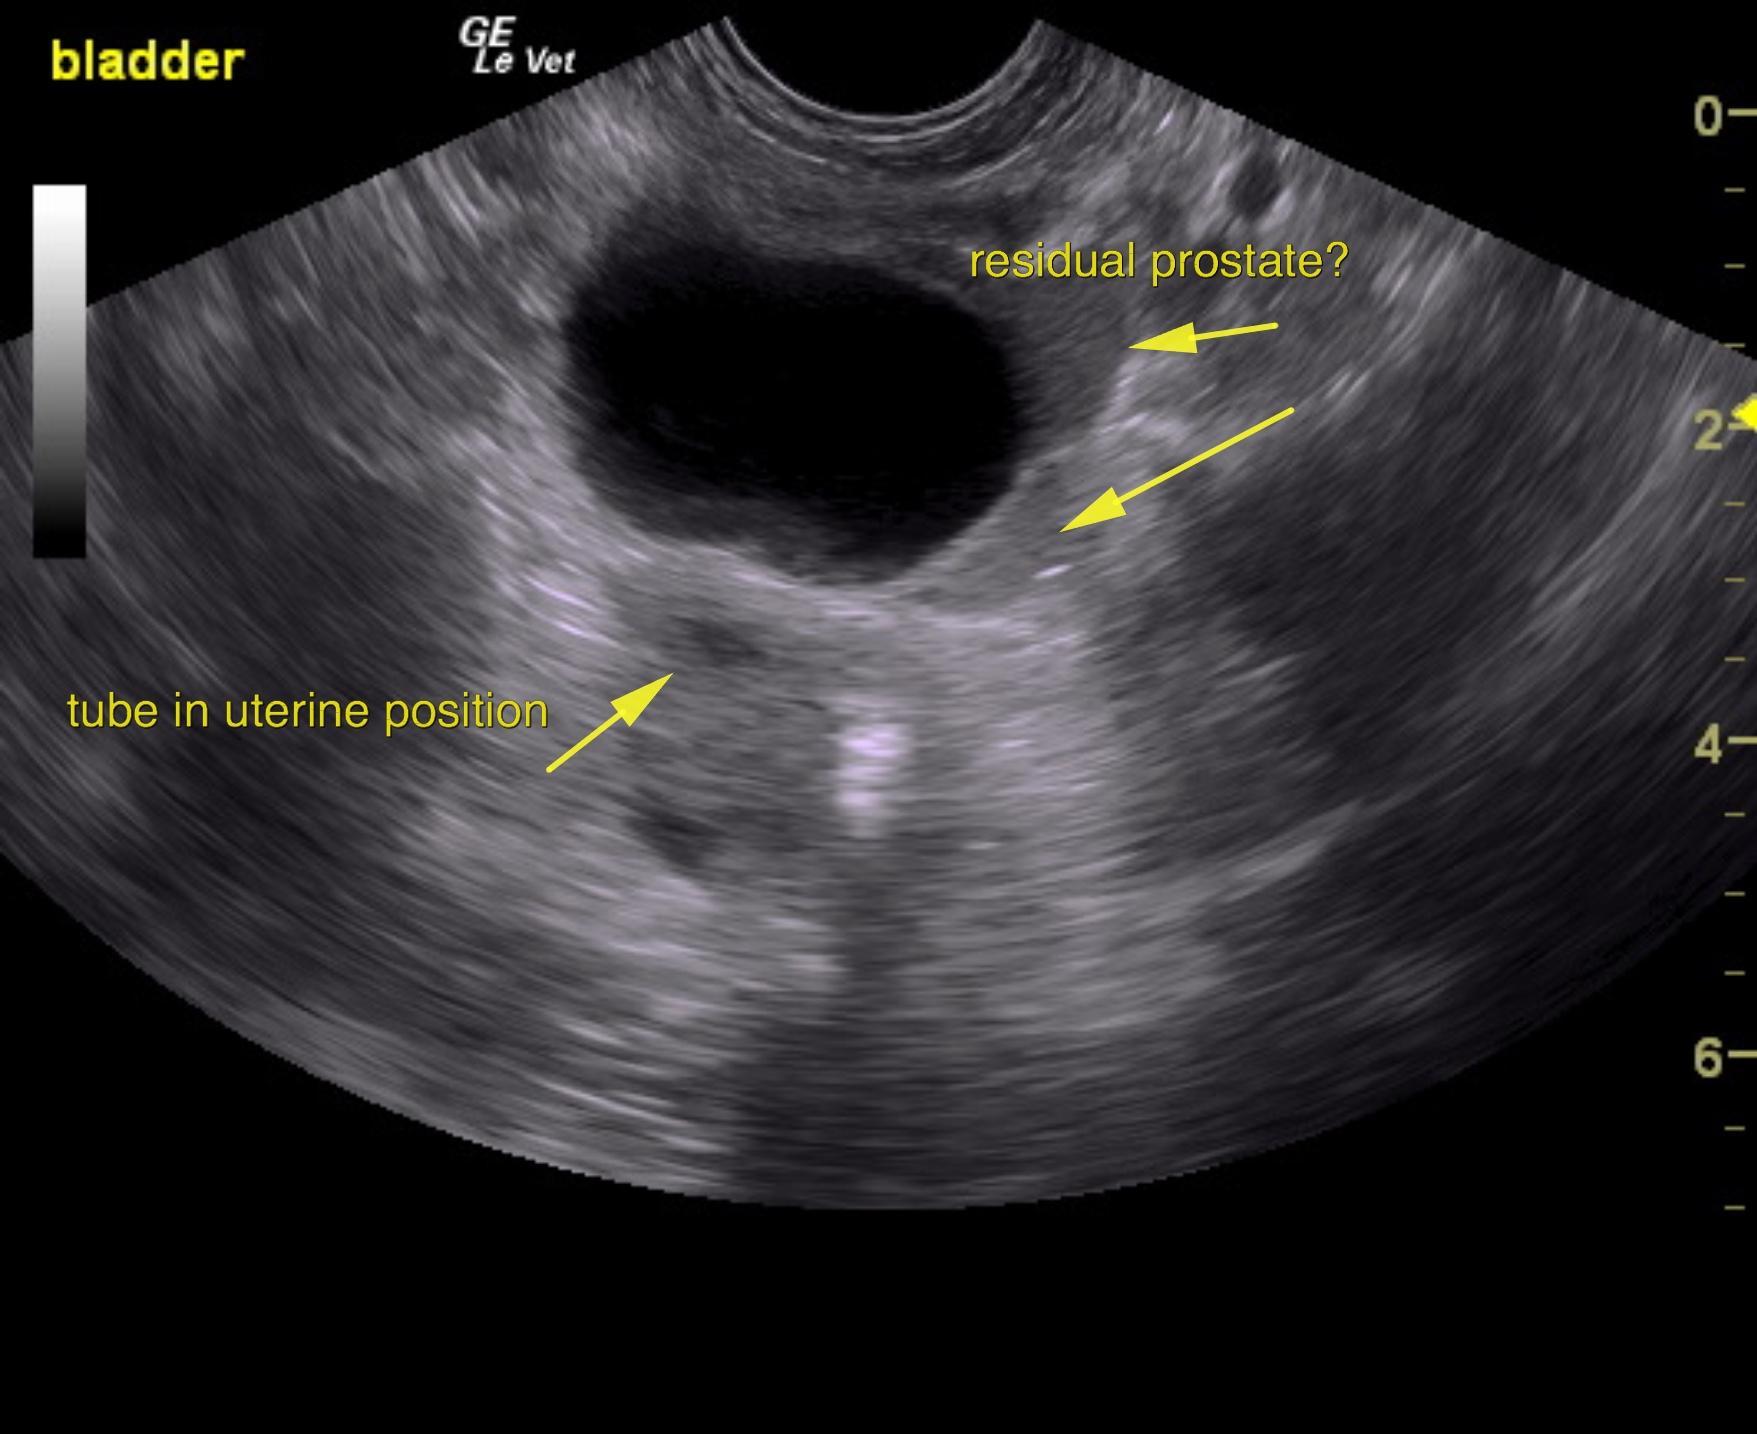

An 11-year-old NM Poodle was presented for evaluation of back pain and dark urine. Urinalysis and blood work were both unremarkable.

Purulent material was obtained on ultrasound-guided centesis without complications. However, reactive mesentery was noted throughout the pelvis. The position of this tube would fit with a uterus. This patient may be a hermaphrodite with secondary pyometra. I cannot make a direct connection from the tubular structure to the prostate itself as they appear to be separate. I recommend exploratory surgery with removal of this structure. The ureters do not appear to be involved. The position and structure would be that of a uterus. Therefore, treatment for pancreatitis and localized infection in the region of the pelvis would be recommended with IV fluid support, broad spectrum antibiotics such as Enrofloxacin and Clindamycin combination as well as exploratory surgery. If the tubular structure is confirmed to be a uterus and hermaphroditism then examination for possible ovaries would also be warranted even though none were visible in the image set. Regardless, this tubular structure necessitates surgical resection.

The urinary bladder itself presented minor thickening and minor debris. A tubular structure was noted in a position between the colon and the urinary bladder with dilation.

Pyometra in neutered male hermaphrodite

Exploratory surgery confirmed pyometra in a neutered male.